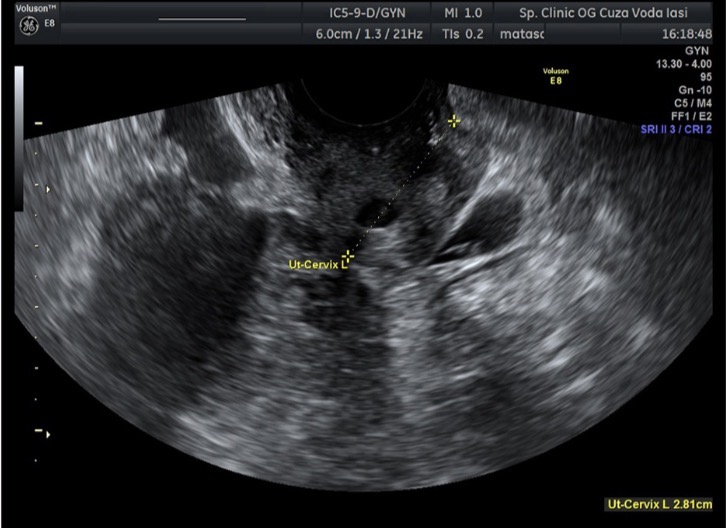

НемедицинаFigure 1. Трансвагинальное УЗИ у 28-летней женщины с левосторонней трубной эктопической беременностью через 8 лет после гистерэктомии.

Гетерогенное, чётко отграниченное образование малого таза с множественными кистозными структурами в непосредственном контакте с влагалищем и мочевым пузырём, без внутритканевой васкуляризации.